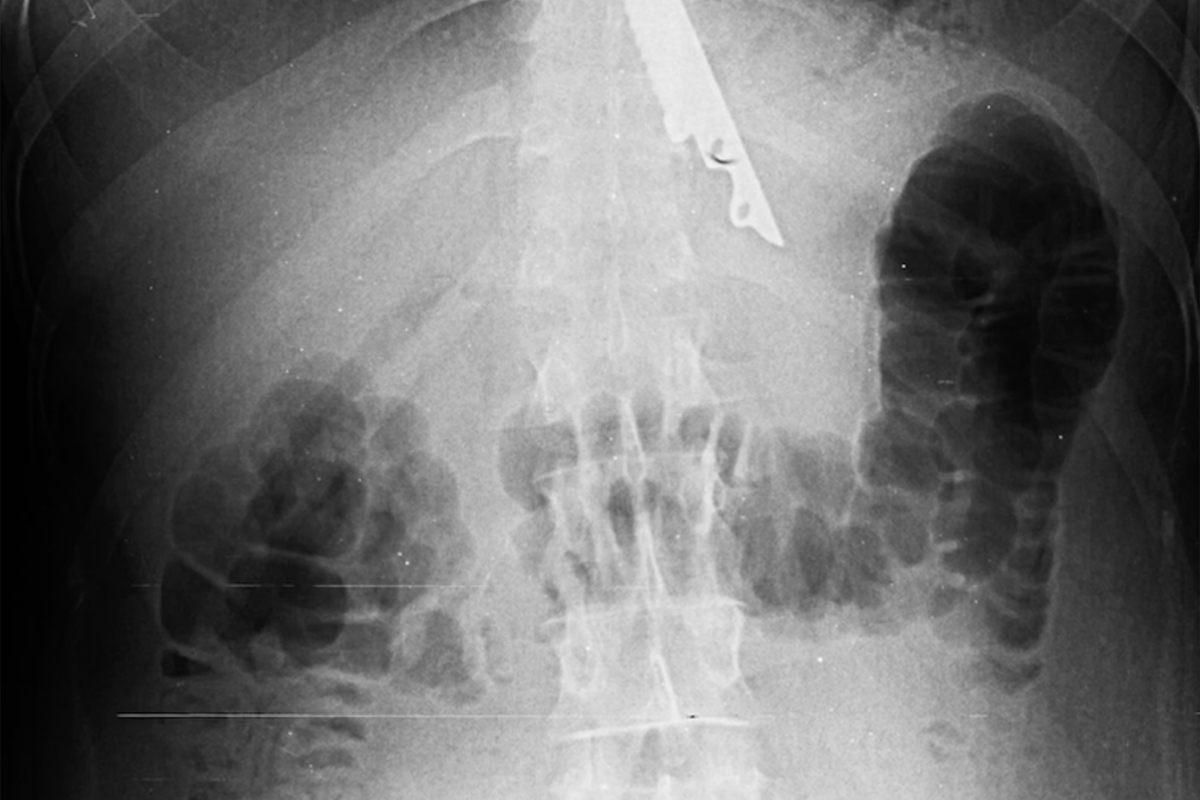

Московские хирурги спасли мужчину с 20-сантиметровым ножом в желудке

В Москве хирурги спасли мужчину с 20-сантиметровым ножом в желудке

В Москве врачи спасли пациента, у которого в желудке после пикника оказался 20-сантиметровый нож. Об этом сообщает НИИ скорой помощи им. Склифосовского.

По информации медучреждения, мужчина во время поедания шашлыка подавился кусочком мяса. Его друзья попытались помочь ему, протолкнув пищу ножом, однако острый предмет также оказался в пищеводе пострадавшего.

В результате пострадавшего доставили в медицинское учреждение, где хирурги извлекли инородный предмет из желудка пациента. Операция прошла успешно, сейчас жизни мужчины ничего не угрожает. Врачи отметили, что случаи проглатывания посторонних предметов часто происходят как по случайности, так и в результате нелепых споров.